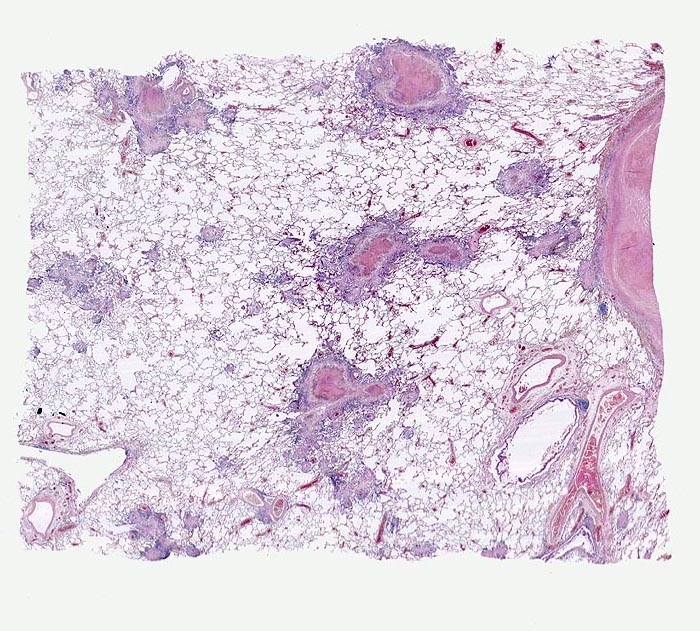

An Tuberkulose erkranken nur ca. 10% der exponierten und infizierten Personen in der Regel innerhalb von zwei Jahren nach Infektion. Eine Tuberkuloseerkrankung (Fortschreiten oder Reaktivierung der Infektion) tritt vor allem im Kleinkindesalter und bei beeinträchtigter Funktion des Immunsystems auf (HIV Infektion, immunsuppressive Therapien, Diabetes mellitus, Raucher, Unterernährung...). Selten verläuft die Primärinfektion progredient mit Entwicklung einer meist einseitigen Ausbreitung der Herde mit Frühkavernenbildung, verkäsender Pneumonie und oft einer hämatogenen Frühstreuung. Die progressive Lymphknotentuberkulose des Primärkomplexes ist der häufigste Ausgangspunkt der lympho-hämatogenen Streuung in der Primärperiode. Die isolierte Organtuberkulose der Lunge wird Lungenphthise genannt. Dabei handelt es sich meist um eine Exazerbation alter, vorwiegend apikaler hämatogener vorübergehend zur Ruhe gekommener Streuherde bei verminderter Resistenzlage oder seltener um eine kontinuierliche phthisische Entwicklung im Rahmen einer hämatogenen Streuung. Eine hämatogene Streuung kann ausgehen von primären oder postprimären, pulmonalen oder extrapulmonalen Herden. Sie kann bei verminderter Resistenzlage jederzeit vorkommen. Das Spektrum reicht von einzelnen kleinen Streuherden bis zur miliaren Aussaat (> 2865) (> 3680) mit bakterienreichen areaktiven käsigen Herden bei der Tuberkulosepsis

Das morphologische Bild ist äusserst variabel. Je nach Abwehrlage, Art und Geschwindigkeit der Ausbreitung entstehen unterschiedlich grosse, teils geschichtete Herde mit unterschiedlichem Grad an Epitheloidzellreaktion, zentraler Nekrose bzw. Vernarbung. Rein produktive Granulome ohne Nekrosen sind Zeichen guter Abwehrlage. Der Begriff Verkäsung bezieht sich auf den makroskopischen Aspekt von Nekrosen, der an Frischkäse erinnert. Exsudative nekrotisierende Granulome entstehen bevorzugt bei schlechter Abwehrlage. In späteren Stadien der Lungentuberkulose unterscheidet man produktive Phthisen mit azinös nodösen Gruppen von bronchogen entstandenen gering verkäsenden Streuherden (Präparat), zirrhotische Phthisen mit gering verkäsenden stark vernarbenden Herden und exsudative Phthisen bei schlechter Abwehrlage. Bei letzterer steht die Verkäsung im Vordergrund. Die bakterienreichen Herde entstehen teils hämatogen, teils bronchogen. Verkäsende Herde sind Ausgangspunkt für die Kavernenbildung. Kavernen stellen die wichtigste Quelle für die bronchogene Streuung dar.